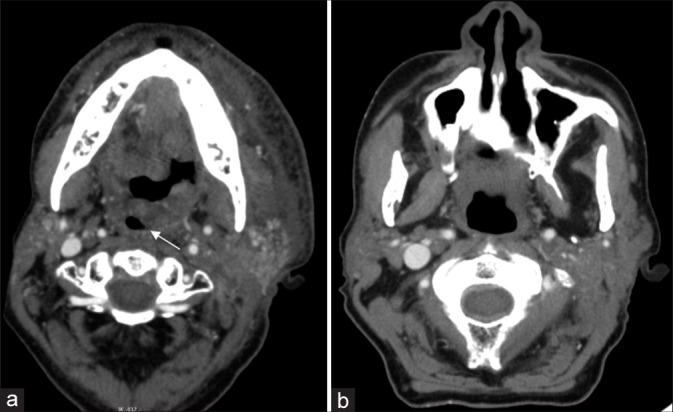

本综述描述了头颈癌(HNCs)急诊病例的放射学表现,包括未确诊和曾接受治疗的患者,重点强调了每次表现的时间紧迫性,以及与相关临床表现和必要治疗的联系,以加强理解和认识。HNC的各种表现将根据其主诉的器官系统来描述。我们将详细介绍每一种疾病的发展和并发症,重点介绍急诊科的临床表现和对诊断至关重要的影像学结果。每个报告将与一个特定的病例一起展示,并展示所获得的精确的计算机断层扫描、磁共振成像、超声或数字减影血管造影图像。病例包括声门肿瘤或转移性颈部淋巴结病引起的气道阻塞;手术并发症血肿或放疗后软组织水肿引起的气道阻塞;肿瘤或淋巴结压迫、颈动脉爆裂、颈动脉狭窄或闭塞等血管并发症;眶间室综合征并发症;骨髓炎和骨放射性坏死的骨科并发症。11例HNC患者与其相关的32张图像。HNC患者在紧急情况下表现出具有挑战性的影像学特征。辨别正确诊断的困难来自复杂的头颈部解剖结构,通常由于出现的晚期和功能状态差而复杂化。放射科医师熟悉常见的HNC急诊表现对于准确诊断和及时治疗至关重要。

This review describes the radiographic findings in emergencies of head and neck cancers (HNCs) in both undiagnosed and previously treated patients, with an emphasis on the temporal urgency of each presentation and in association with the relevant clinical presentation and necessary treatments to enhance understanding and recognition. The various presentations of HNC will be described by the organ system of their presenting complaint. The development and complications of each will be elaborated, with a focus on the clinical presentation in the emergency department and the imaging findings that are critical to recognize in making the diagnosis. Each presentation will be exhibited with a specific patient case and the exact computed tomography, magnetic resonance imaging, ultrasound, or digital subtraction angiography images obtained will be shown. Cases include airway obstruction due to glottic tumor or metastatic cervical lymphadenopathy; airway obstruction due to surgical complications of hematoma, or post-radiation soft-tissue edema; vascular complications of tumor or nodal compression, carotid blowout, carotid stenosis, or occlusion; orbital complications of compartment syndrome; and orthopedic complications of osteomyelitis and osteoradionecrosis. Eleven HNC patient cases are presented with their associated 32 images. HNC patients present with challenging imaging features in the emergent setting. Difficulty in discerning the correct diagnosis arises from the complex head and neck anatomy, often compounded by an advanced stage at presentation and poor functional status. Radiologist familiarity with common HNC emergent presentations is essential for accurate diagnosis and timely treatment.